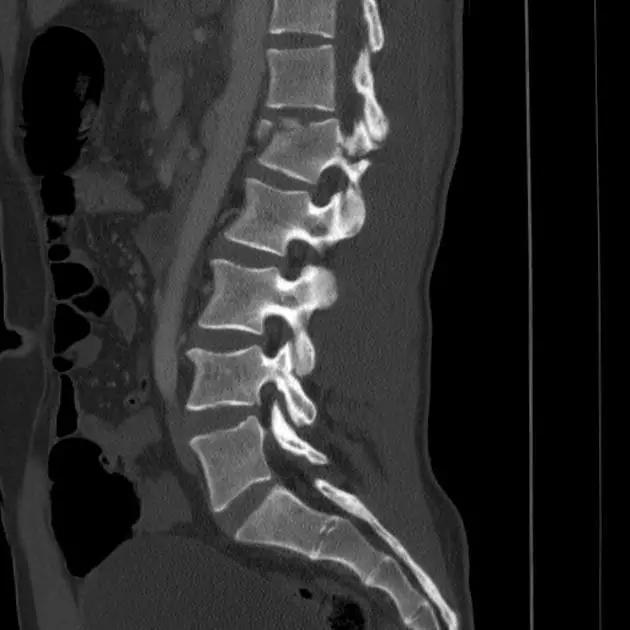

脊柱骨折

1. Burst 骨折

椎体轴向压力造成的骨折,通常发生骨折碎片向外侧的移位。可以发生在颈椎、胸椎或腰椎。

(来源:Radiopaedia)

3. Chance 骨折

胸腰段椎体的分离性骨折,伴随脊髓、神经根、椎体的水平方向的崩裂骨折。又称座带骨折(seatbelt fracture)。

由 Chance 于 1948 年首先描述此骨折,故文献又常称 Chance 骨折,为一种屈曲拉伸骨折。典型的损伤机制为汽车座带束于患者腰腹部,当高速行驶的汽车突然减速或撞车时,座带支点以上的躯干屈曲,前冲力还同时产生一个向前拉伸的力量。将椎体由后方向前撕裂,骨折线横过椎体、椎弓根和椎板,椎体后部的韧带完全撕裂。有时前纵韧带亦可撕裂,常合并有神经系统的症状。